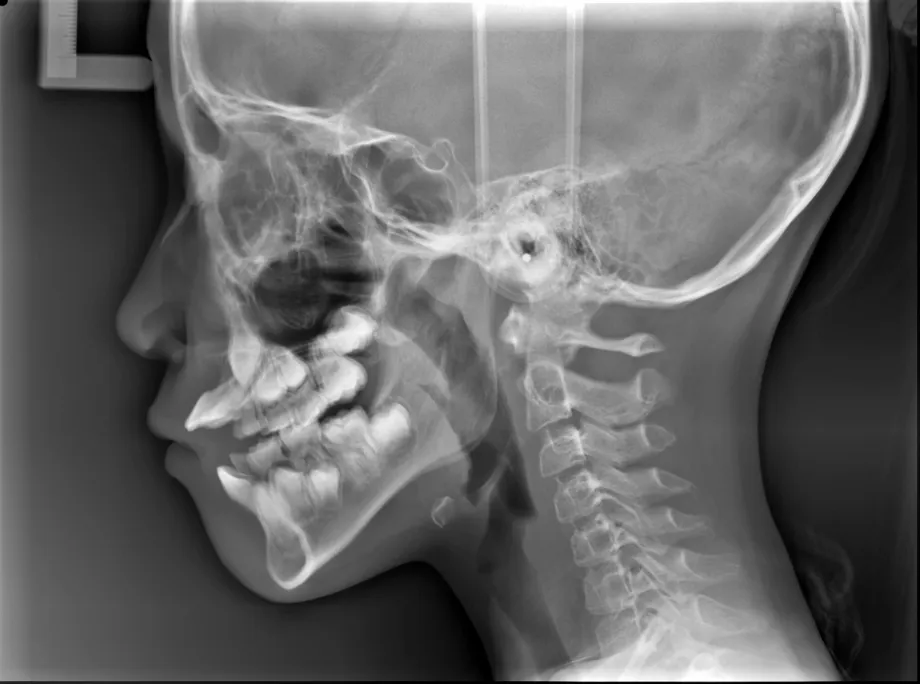

【治療前】

【治療開始から1年後】